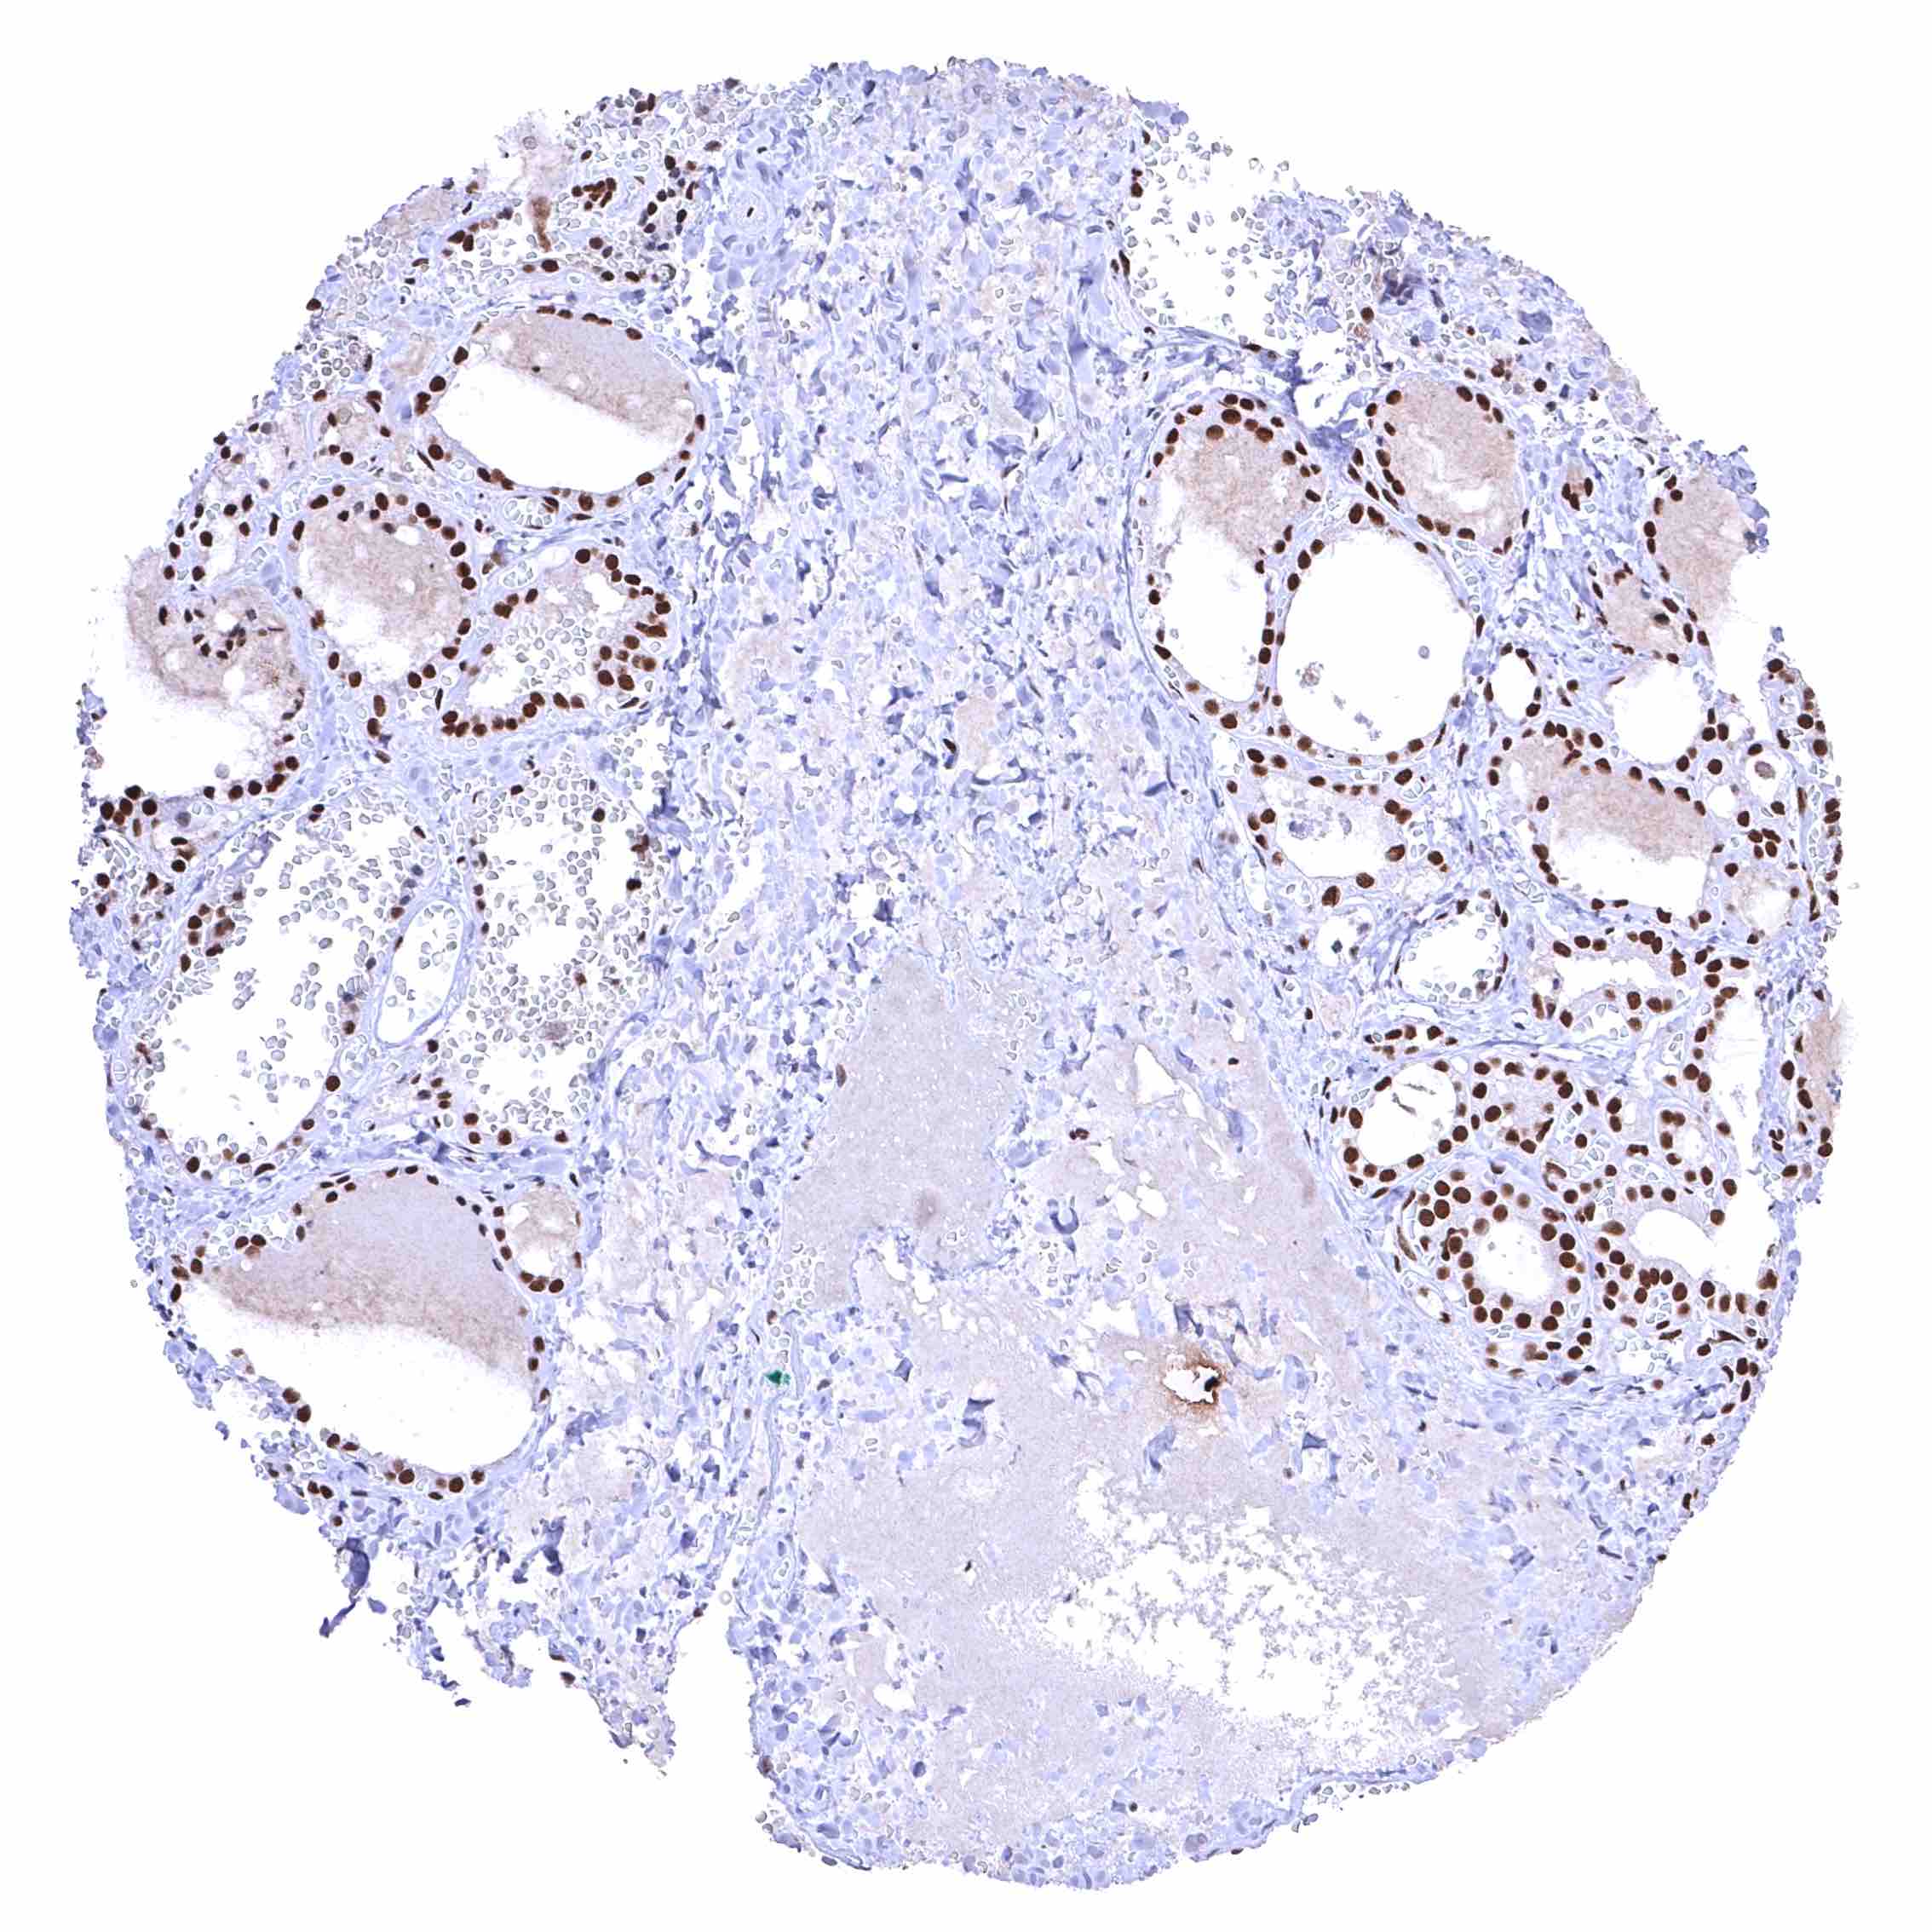

Thyroid gland – Strong nuclear BRD4 staining of epithelial cells.